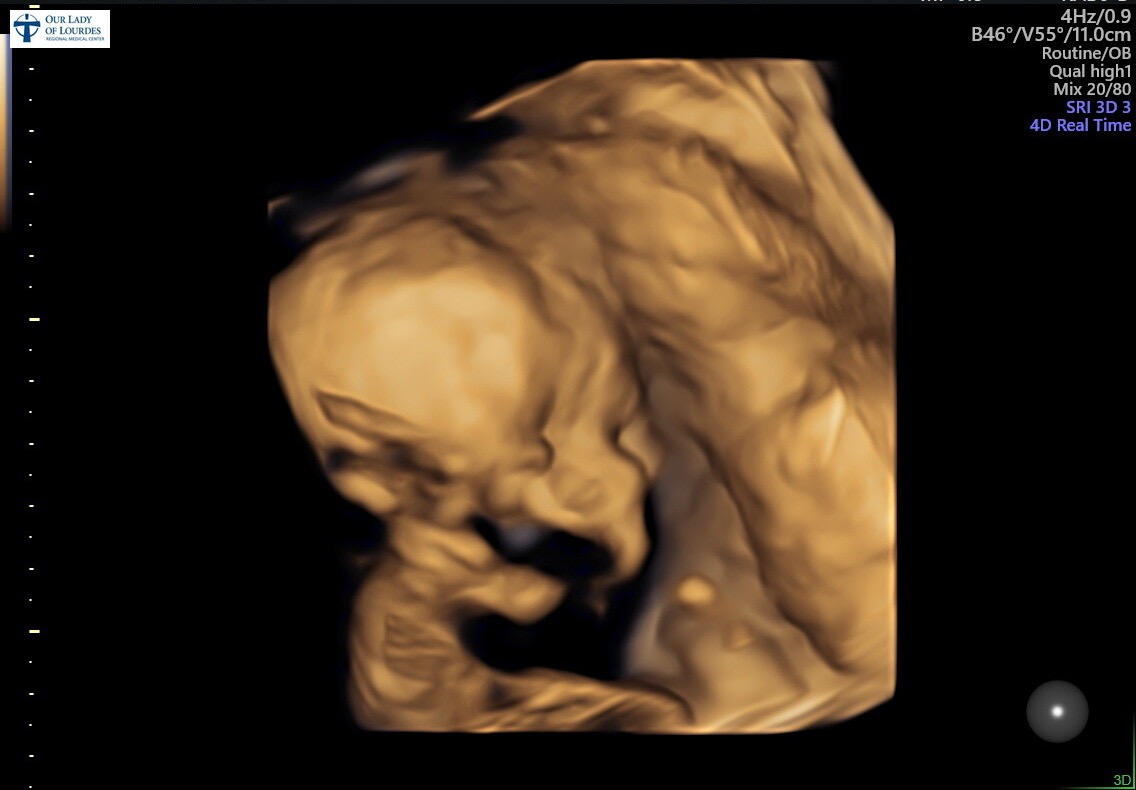

Taiah and Destin are in the final stretch of pregnancy, but instead of being able to relax and enjoy these last weeks, they’ve been faced with something really tough. Their baby has been diagnosed with fetal supraventricular tachycardia (SVT), a condition where the baby’s heart beats dangerously fast. Because of this, Taiah has had to spend a lot of time in the hospital, and working consistently just isn’t possible right now.